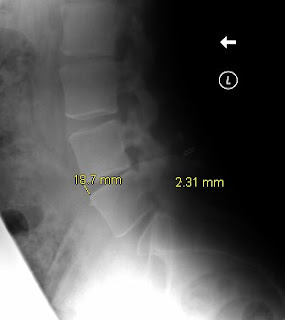

The X-Rays following my 6 month visit to the surgeon were finally sent to me and I've posted them underneath.

Here are the X-rays:-